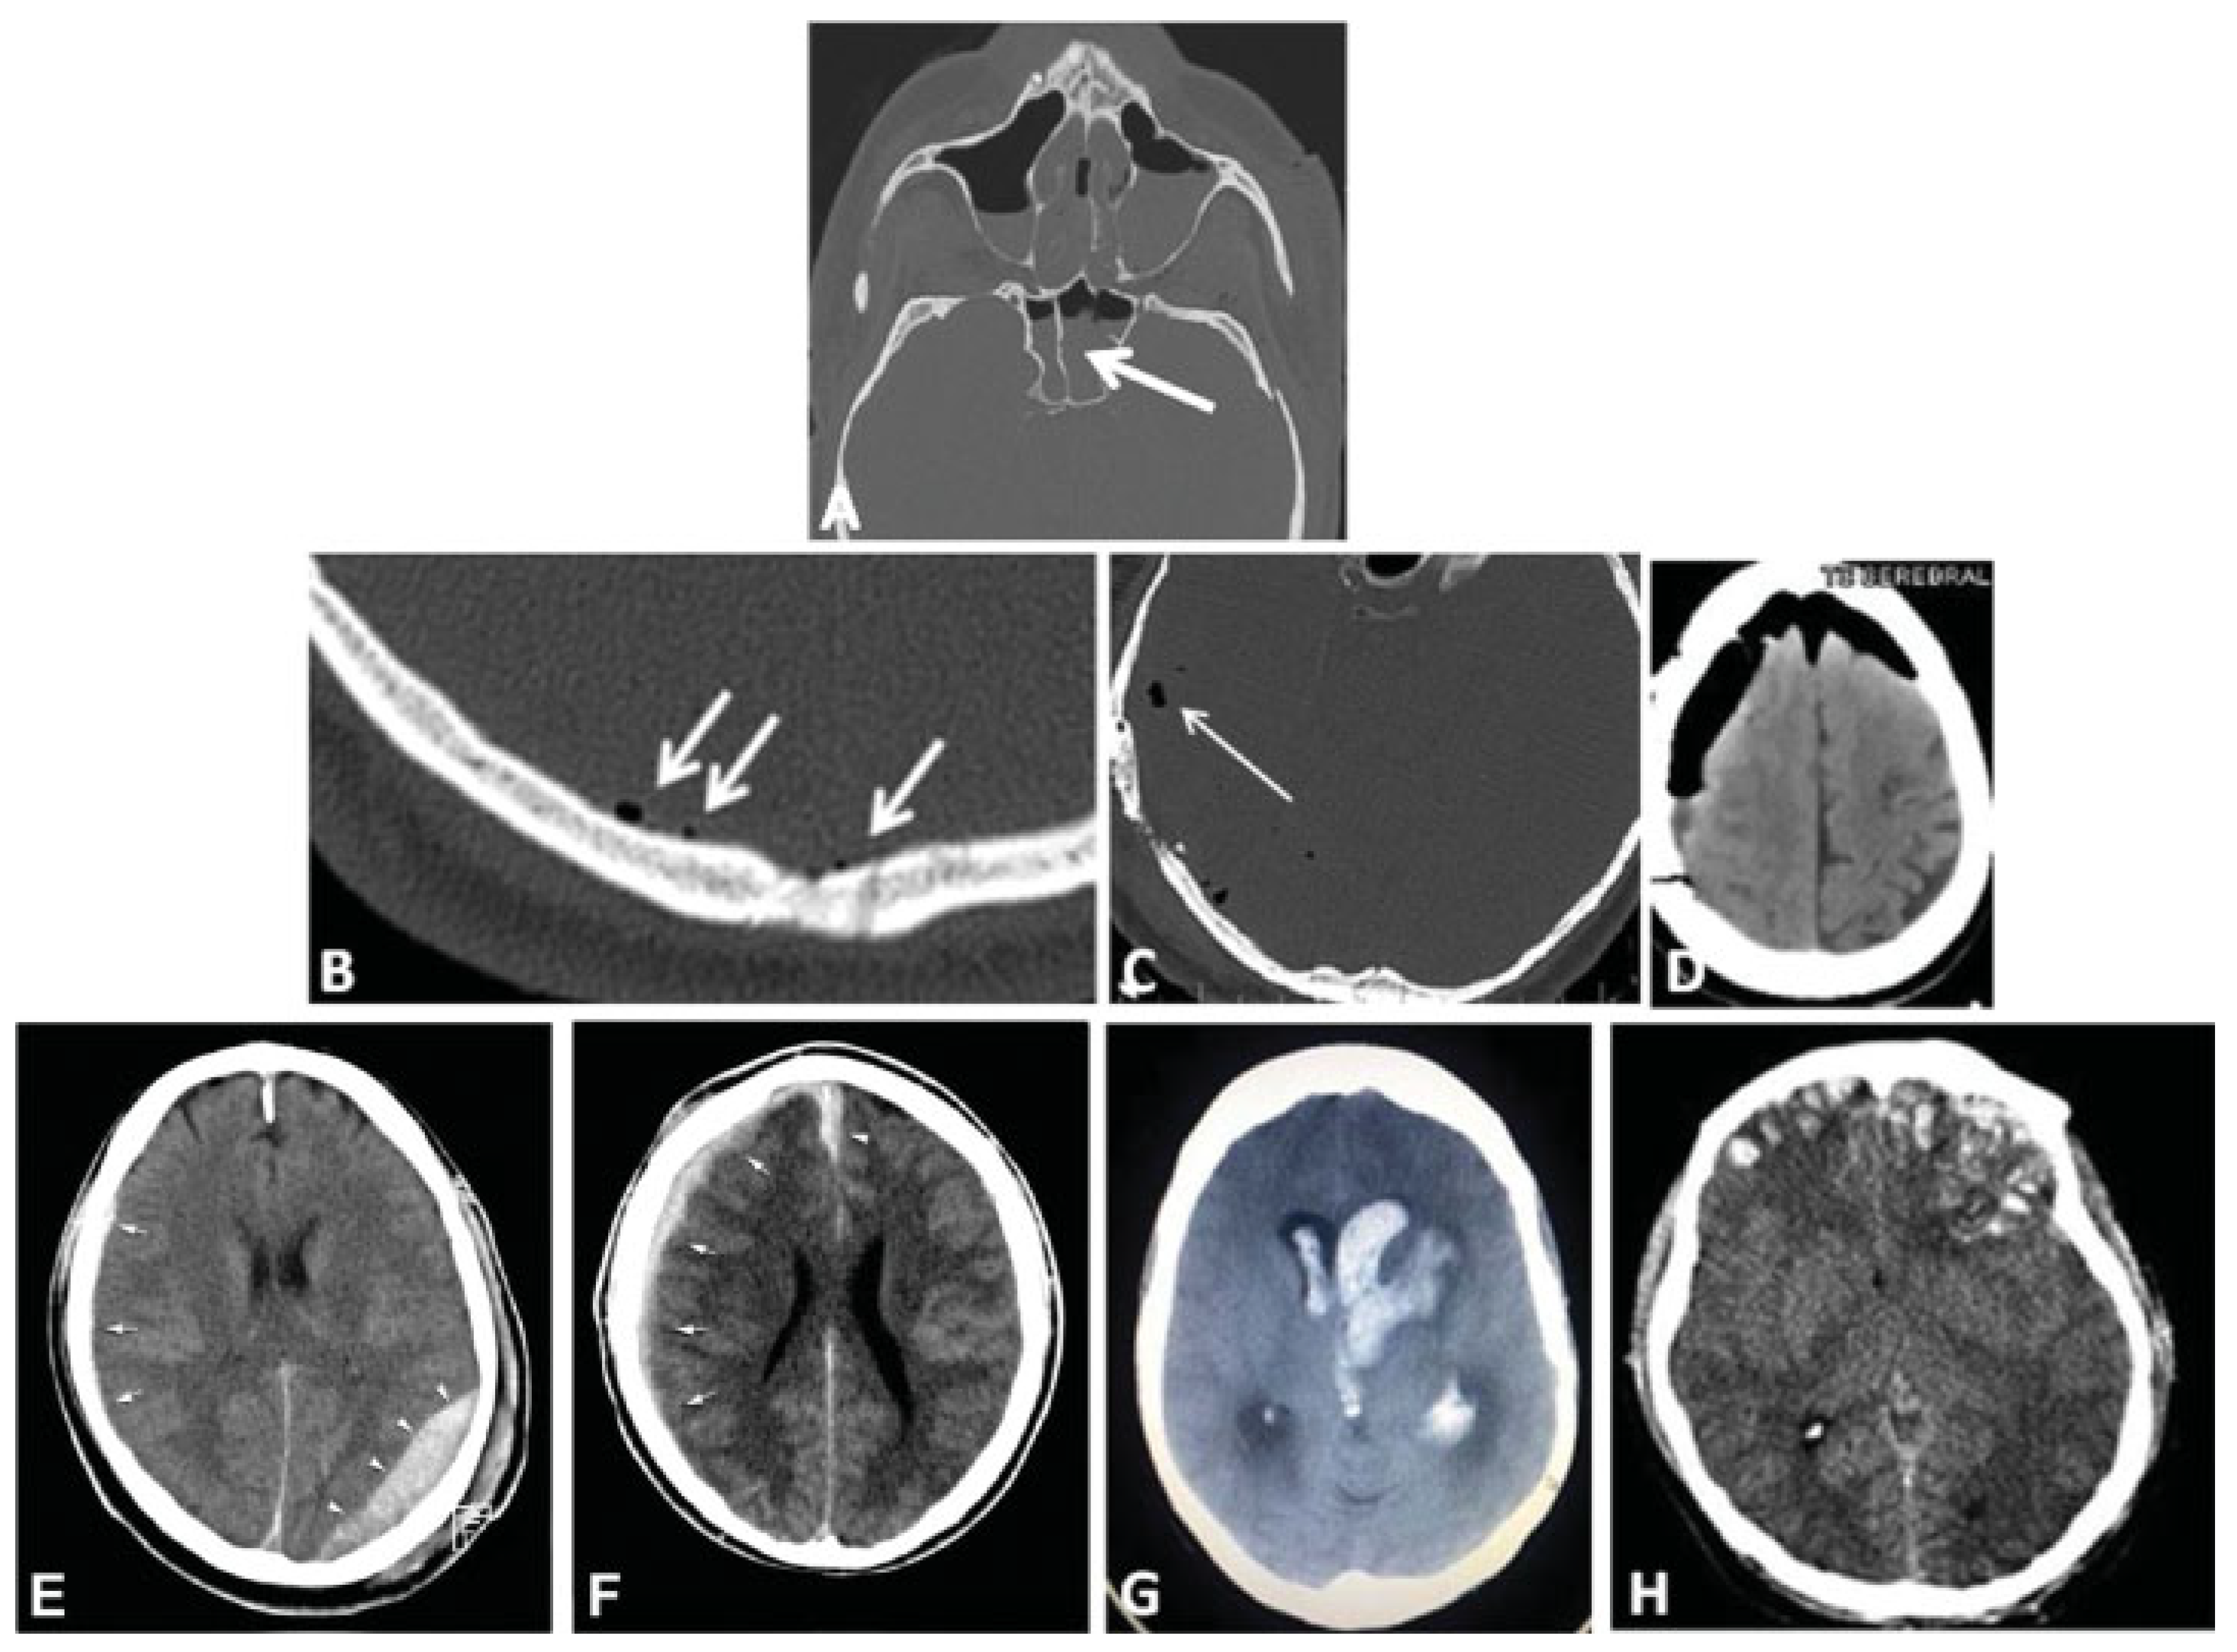

This coding system allows description of most relevant fracture patterns as illustrated in the case examples, such as the differentiation between unilateral or bilateral fracture patterns. In a series of three case examples, we illustrate the coding of a case with multiple cranial vault fractures (Figure 5), a single skull base fracture extending into the temporal cranial vault (Figure 6) and a right occipital and temporal cranial vault fracture extending into right middle fossa skull base (Figure 7). A range of additional fracture patterns are presented in a special case appendix as electronic supplement to this issue of the Journal (www.aocmf.org/classification).

Figure 5. Multiple cranial vault fractures. (A–F) Multiple cranial vault fractures. The right sided fractures involve the frontal and parietal vault with comminution and depression and extension inferiorly into the temporal cranial vault. Similarly, on the left, there is a linear parietal vault fracture that appears to continue into the temporal bone. (G) There is extension of these fractures into the left and right sphenoid bone. Imaging: Computed tomographic axial views. (H) Level 3 code: 93 S0.m.S0, 94 F1.P1.T0.m.T0.P0, This case example CMTR-93-94-001 is made available electronically for viewing using the AOCOIAC software at www.aocmf.org/classification.